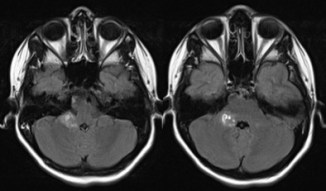

elle peut être très évocatrice, montrant une tumeur spontanément hyperdense en scanner, avec une prise de contraste hétérogène et une hypercellularité bien montrée par la séquence en diffusion.

l’aspect radiologique peut cependant être trompeur.

on recherche systématiquement des métastase par l‘IRM cranio-spinale.